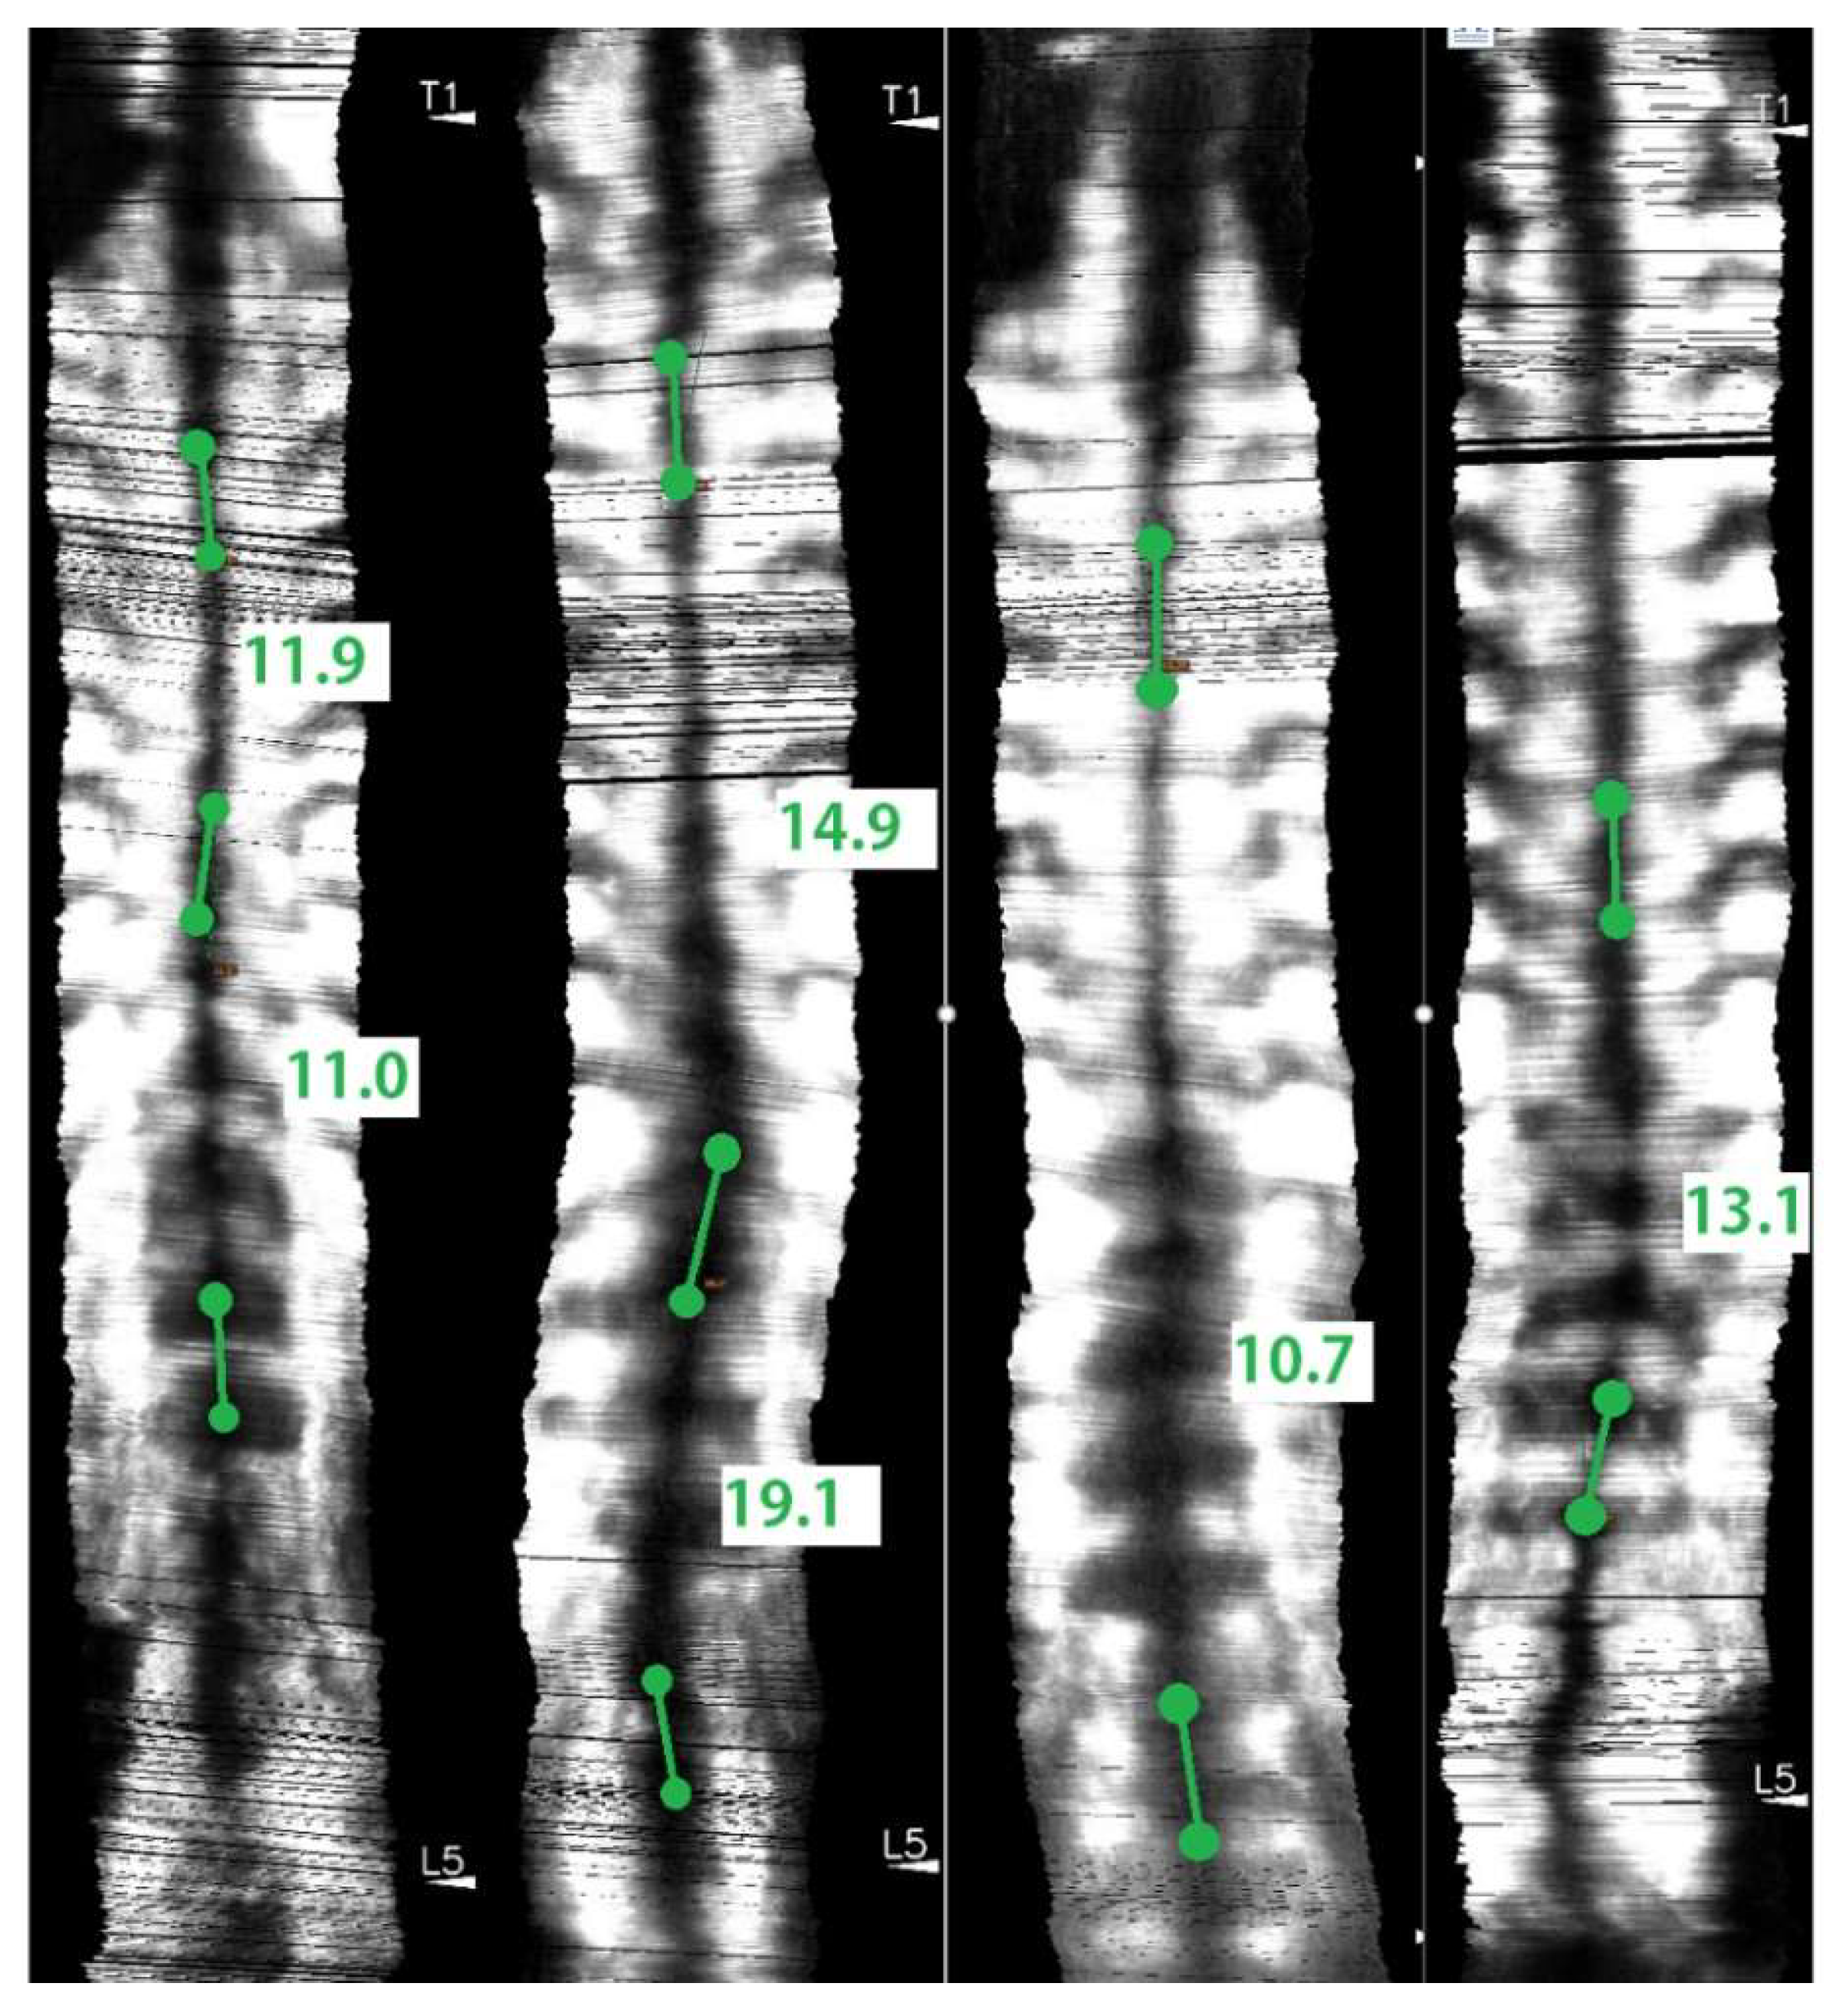

- Cheung, C.W.J.; Zhou, G.Q.; Law, S.Y.; Mak, T.M.; Lai, K.L.; Zheng, Y.P. Ultrasound Volume Projection Imaging for Assessment of Scoliosis. IEEE Trans. Med. Imaging 2015, 34, 1760–1768. [Google Scholar] [CrossRef]

- Zheng, Y.P.; Lee, T.T.Y.; Lai, K.K.L.; Yip, B.H.; Zhou, G.Q.; Jiang, W.W.; Cheung, J.C.W.; Wong, M.S.; Ng, B.K.W.; Cheng, J.C.Y.; et al. A reliability and validity study for Scolioscan: A radiation-free scoliosis assessment system using 3D ultrasound imaging. Scoliosis Spinal Disord. 2016, 11, 13. [Google Scholar] [CrossRef]

- Wong, Y.S.; Lai, K.K.L.; Zheng, Y.P.; Wong, L.L.; Ng, B.K.W.; Hung, A.L.H.; Yip, B.H.K.; Chu, W.C.W.; Ng, A.W.H.; Qiu, Y.; et al. Is Radiation-Free Ultrasound Accurate for Quantitative Assessment of Spinal Deformity in Idiopathic Scoliosis (IS): A Detailed Analysis With EOS Radiography on 952 Patients. Ultrasound Med. Biol. 2019, 45, 2866–2877. [Google Scholar] [CrossRef] [PubMed]